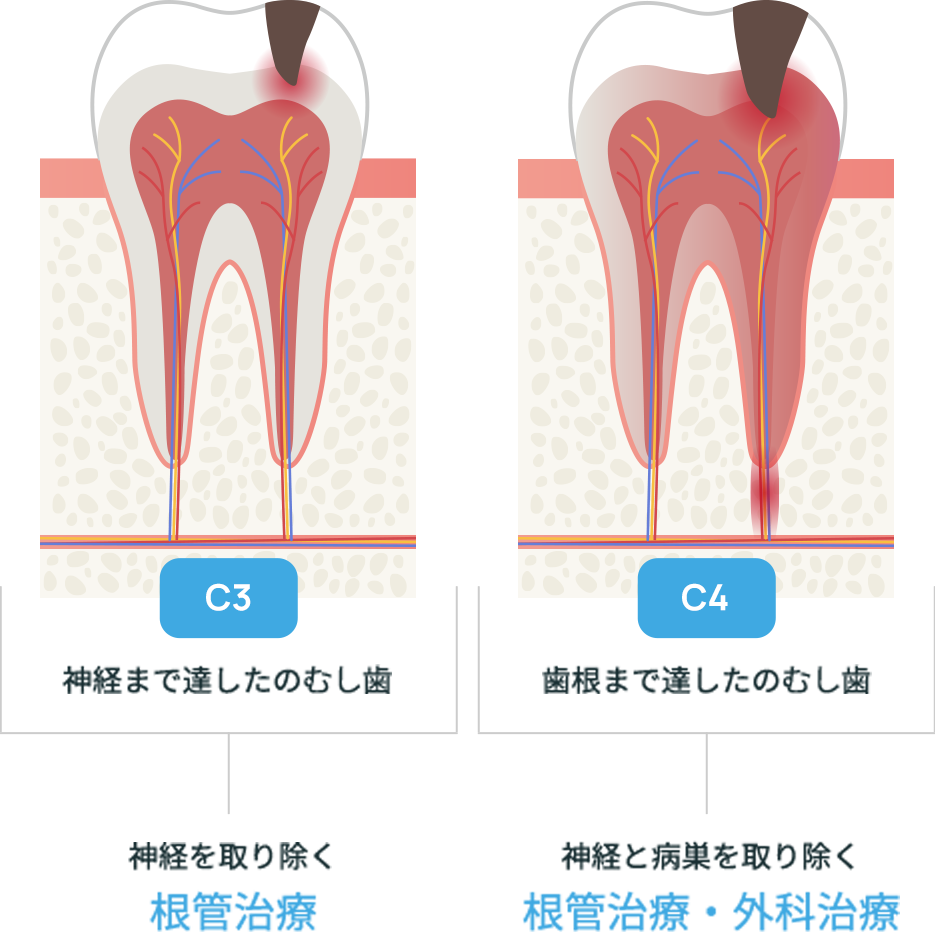

進行度によって変わるアプローチ

むし歯は進行度によって治療方法が変わってきます。状態を見極めて治療を選択します。

根管治療

歯の中には「歯髄(しずい)」と呼ばれる神経や血管を含む組織があります。むし歯が進行して歯髄が感染したり、壊死したりすると歯髄を取り除く根管治療が必要になります。これを一般的に「神経を抜く」と表現します。

外科治療

根管治療では完治が難しいと判断した場合には、外科的処置を行い、感染した歯髄や血管、また病巣を除去します。感染した歯髄や血管を除去し消毒すれば抜歯をせずに歯を残すことが出来ます。